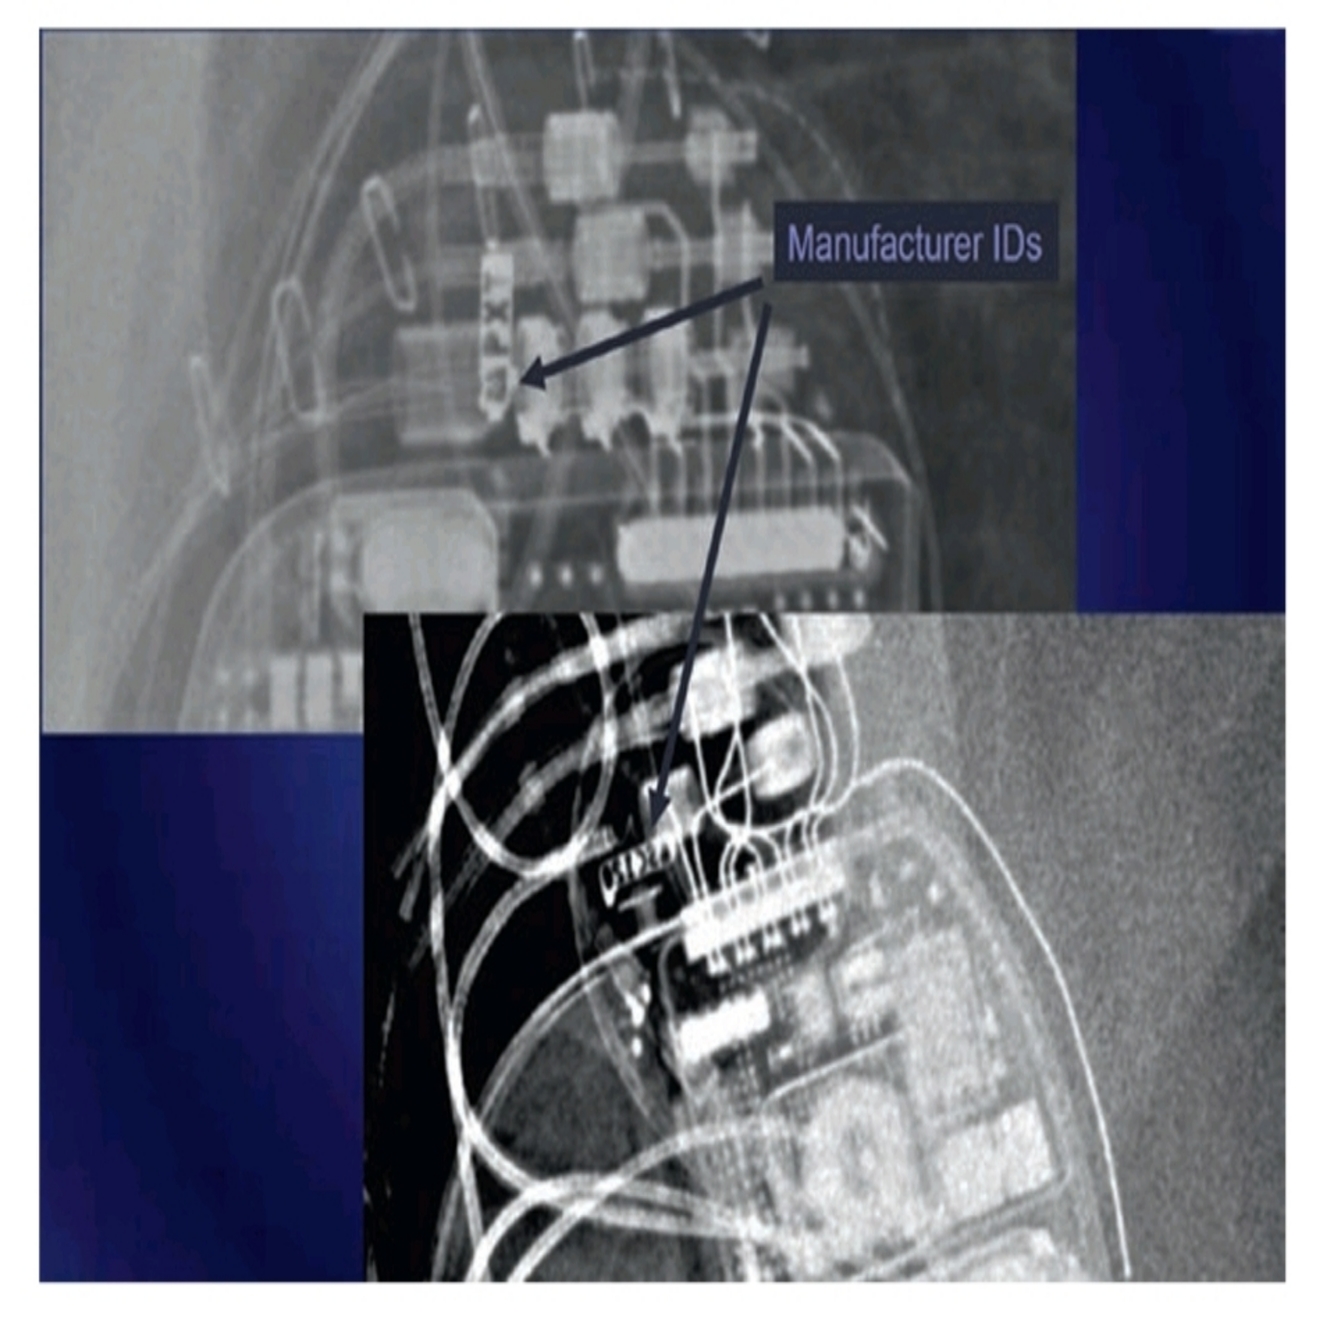

(a) The radiographic image of a pacemaker would show (See Fig.46.2):

(b) The radiographic image of an ICD would show above image:

• Larger generator.

• Prominent right ventricular lead, otherwise known as shock coils.

They appear as two metallic segments along the length of the ICD lead.

(c) The radiographic image of a BiV ICD would show (See Fig.46.4):

• Larger generator

• Prominent right ventricular lead (shock coils)

• Right atrium lead

• Coronary sinus lead

Manufacturer ID can be seen in the CXR as well